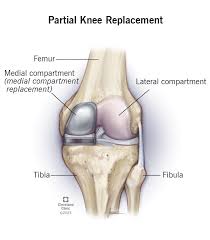

Partial knee replacement replaces only the damaged portion of the knee joint. Unlike total knee replacement, healthy bone and cartilage remain intact. Consequently, knee movement feels more natural after surgery.

Partial knee replacement suits patients with arthritis limited to one knee compartment. Osteoarthritis remains the most common indication. Additionally, early degenerative changes and localized cartilage damage may require surgical correction.

The procedure begins with detailed preoperative planning. Dr. Utsav Agrawal evaluates knee alignment, ligament stability, and cartilage condition carefully. This preparation ensures accurate implant selection.

During surgery, only the damaged joint surface is removed. Then, high-quality implants replace the affected area. The remaining knee structures stay untouched. Advanced operation theatre facilities ensure safety and precision throughout the procedure. Consequently, surgical outcomes remain consistent and reliable.